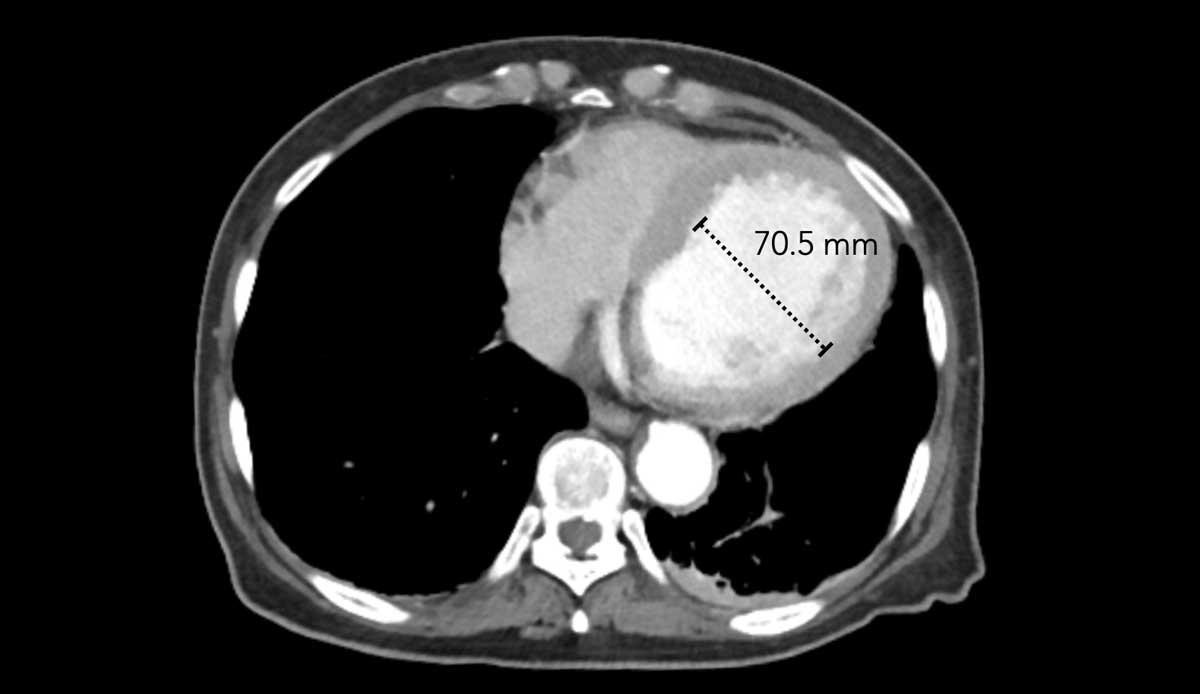

Hình ảnh

Tình cờ phát hiện tâm thất trái giãn nặng.

Đường kính ngang của tâm thất trái > 70 mm.